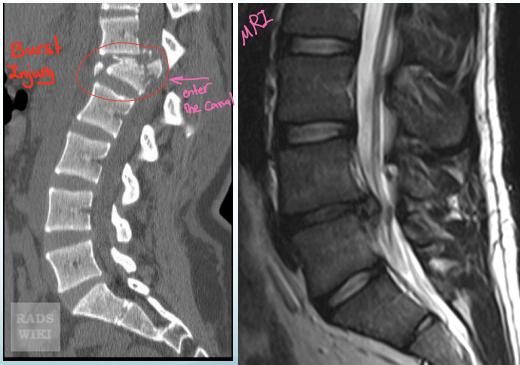

Advanced Imaging Modalities

- CT Scan: Shows bony structures in detail

- MRI: Shows soft tissues, discs, and spinal cord (gold standard for disc pathology)